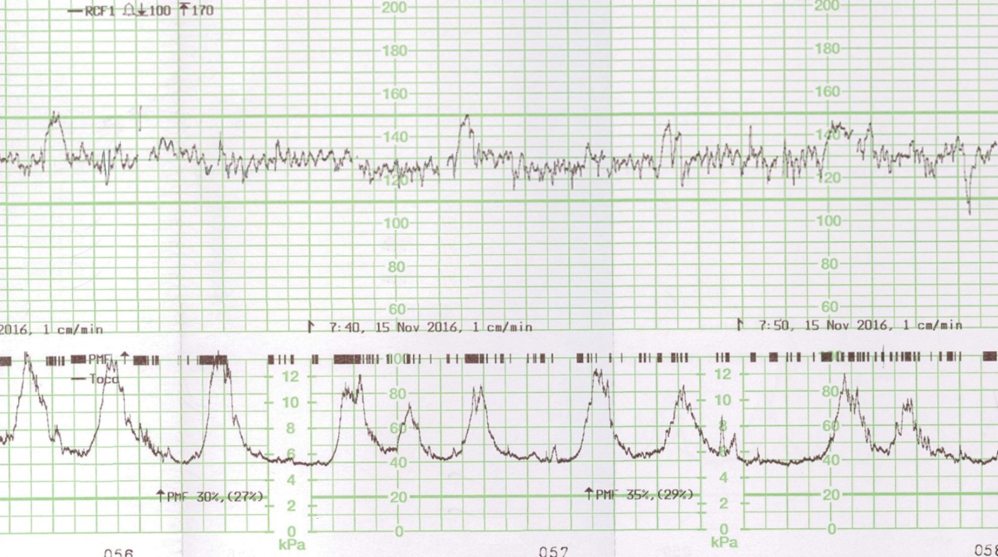

À 30 SA, Mme L. consulte aux urgences adressée par son échographiste avec la courbe de croissance et les images suivantes.

Figure 1 (Rodolphe Matias de Sousa, La Revue du Praticien)

Figure 2 (Rodolphe Matias de Sousa, La Revue du Praticien)

À l’arrivée : pression artérielle (PA) = 140/80 mmHg ; fréquence cardiaque (FC) = 100 bpm ; température (T°) = 37,2°C ; bandelette urinaire (BU) : protéinurie +.

Il existe une franche cassure de la courbe, le fœtus est passé au troisième percentile. L’échographie en figure 1 est un écho-Doppler de l’artère ombilicale. Elle montre une diastole ombilicale nulle. Il s’agit donc d’un RCIU et non d’un fœtus petit pour l’âge gestationnel.

Il s’agit vraisemblablement d’un RCIU, probablement d’origine vasculaire maternelle secondaire à la microangiopathie de la drépanocytose (hypoxie placentaire chronique).